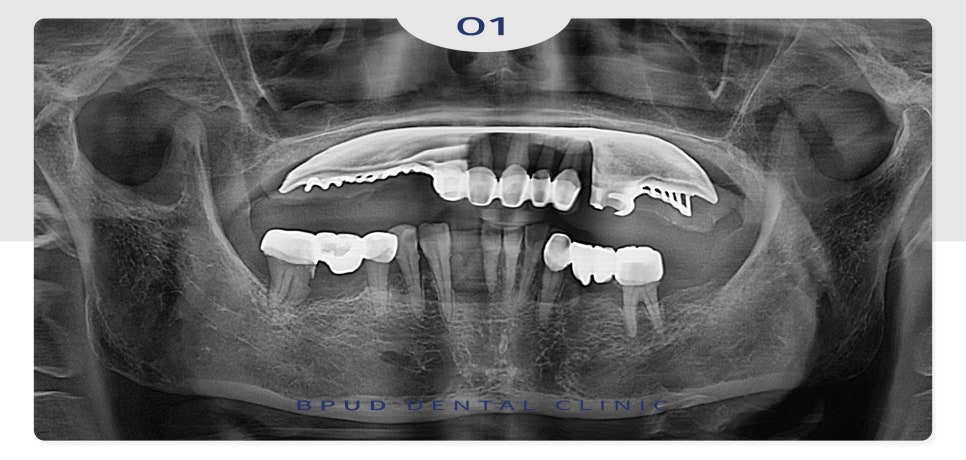

오늘은 부분 틀니를 사용하시다가

전체 임플란트로 교체하신

환자분을 소개해 드리려고 합니다.

위 환자분께서는 오래전부터

위쪽 부분 틀니를 사용 중이셨고

아래 앞니가 자연적으로

발치되신 상태로 틀니를 지지하고

남아 있는 치아들의 동요도도

심하신 상태였는데요.

23.08.31

전체적인 치주염도 심하신 편이라

발치 후 전체 임플란트를 진행하시기로

계획을 수립하였는데요.

환자분의 경제적인 상황을 고려하여

적은 비용으로 식립을 원하셨으며

전체적인 악궁이 크지 않아

필요한 수만큼만 위쪽 7개, 아래쪽 6개로

인공치근을 식립하였는데요.

수술에 대한 두려움이 크셔서

전체적으로 발치한 후

전악 임플란트와 양쪽 상악동 거상술,

전체 뼈이식을 진행하였습니다.